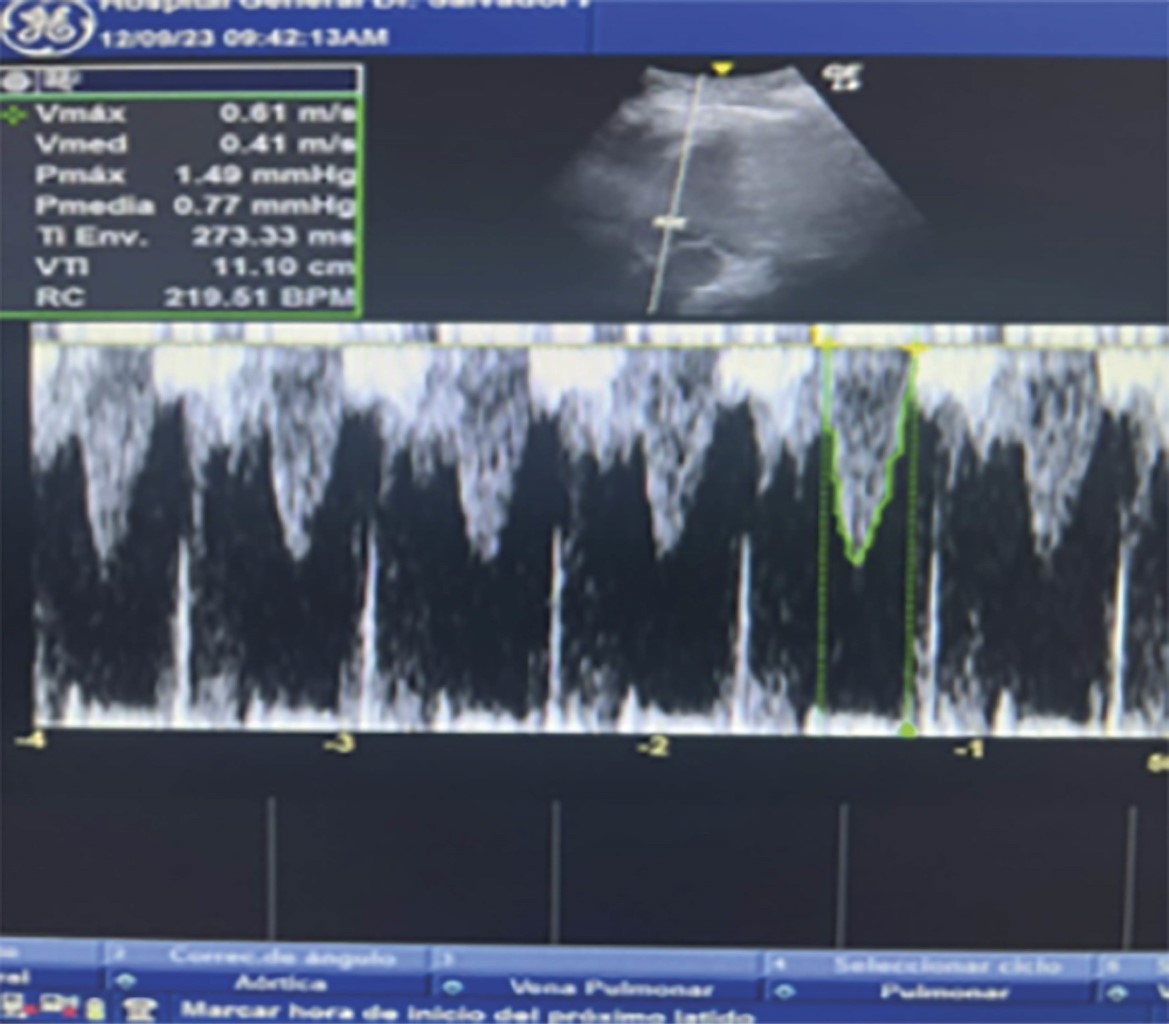

Durante su evolución, se evidencia deterioro hemodinámico con aumento de requerimiento de vasopresores con disminución de SvO2, en la ecocardioscopia se observa hipocinesia del ventrículo izquierdo con una integral velocidad tiempo de 11.1 cm/s, y diámetro de tracto de salida del ventrículo izquierdo de 1.65 cm, con gasto cardiaco de 2.38 L/min (Figura 1 y 2) como deterioro del estado ácido-base con presencia de acidosis metabólica de anión gap elevado (Tabla 3) concomitante con acidosis metabólica de anión gap normal.

Figura 2